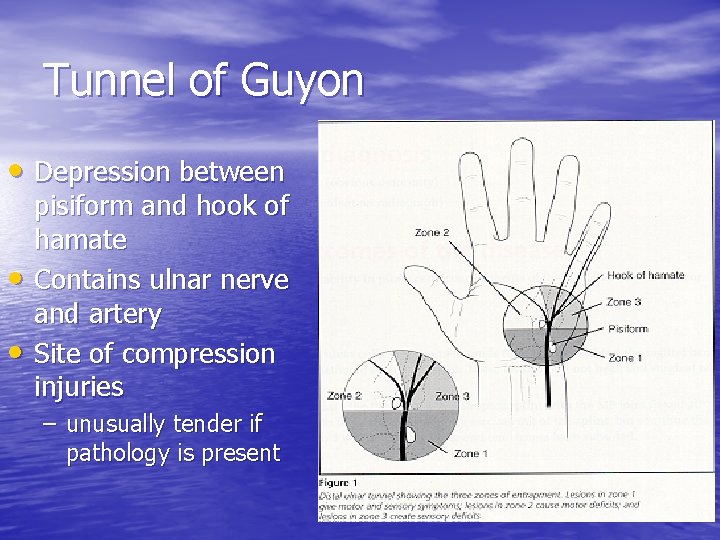

Tunnel of Guyon • Depression between • • pisiform and hook of hamate Contains ulnar nerve and artery Site of compression injuries – unusually tender if pathology is present